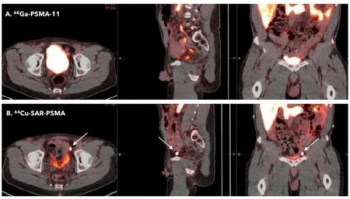

The PSMA PET agent 64Cu SAR-bisPSMA detected a higher number of prostate cancer lesions and had a significantly higher SUVmax and SUVmean than 68Ga PSMA-11 PET/CT, according to initial data from a prospective multisite study presented at the recent Society of Nuclear Medicine and Molecular Imaging (SNMMI) conference.